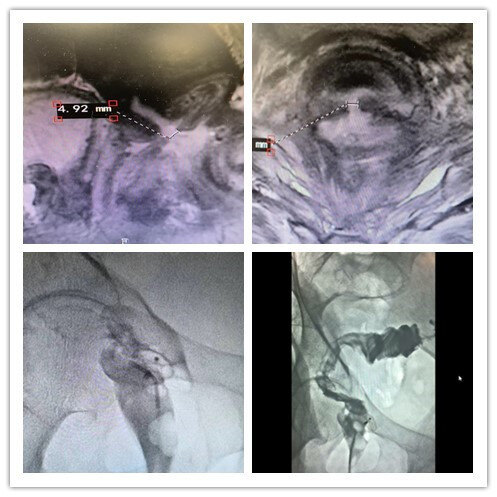

直腸陰道瘺(RVF)是直腸和陰道兩上皮表面之間的先天性或后天性通道,臨床較為少見。主要臨床表現(xiàn)為陰道排氣排便,嚴(yán)重時(shí)大便不能自控。一般無法自愈,大部分患者需要手術(shù)干預(yù)。由于病變部位局部解剖的特殊性和復(fù)雜性,導(dǎo)致手術(shù)難度大,若處理不當(dāng)會(huì)導(dǎo)致反復(fù)感染、復(fù)發(fā)率高,往往導(dǎo)致患者難言的病痛,生活質(zhì)量下降。目前內(nèi)科及外科均無較好治療方法,而介入治療方法創(chuàng)傷小,方法簡單,療效明確?;颊?,女,50歲,直腸腫瘤放療術(shù)后,出現(xiàn)直腸陰道瘺,每天從陰道排出糞液,生活質(zhì)量較差。介入封堵后恢復(fù)正常生活。